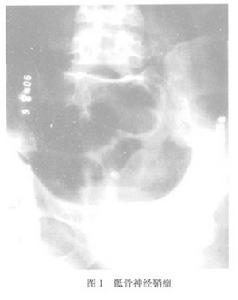

X線所見為均勻的溶骨性骨質破壞,而邊界清晰並可見一薄層硬化骨。腫瘤使骨質膨脹,甚至穿破骨外形成軟組織腫瘤。大的腫瘤可呈多房性,但病變區內無鈣化或骨化。如起源於骨膜則自骨外向骨內破壞形成壓跡,甚至穿破骨質。CT示神經鞘瘤表現為密度不均勻的腫塊其密度從接近於水的密度到肌肉的密度不等邊界整齊,造影后呈不規則增強MRI圖像上亦為信號不均勻腫塊。T1加權信號有高有低若腫塊囊性變或壞死時T2加權可表現為明顯信號。神經鞘瘤只靠影像學表現難以確診椎管內神經鞘瘤可經椎管造影幫助診斷,可見神經孔擴大。